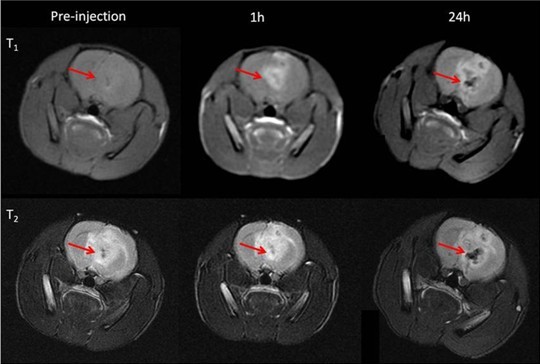

MOF结构钴氰酸锰纳米立方块在小鼠脑部肿瘤部位的磁共振成像应用